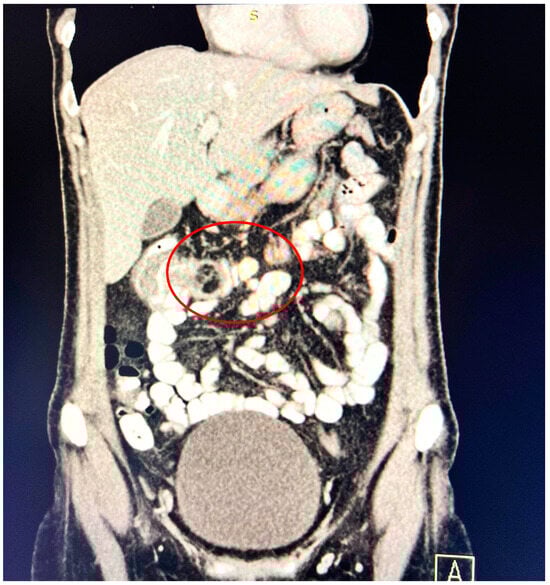

A contrast-enhanced computed tomography (CT) scan conducted on the day of admission revealed circumferential parietal thickening of a maximum of 21 mm at the hepatic flexure of the colon. This thickening extended over a length of approximately 45 mm, resulting in filiform, axial stenosis of the lumen, without any overlying distension of the colonic frame. The parietal thickening was moderately iodophilic and accompanied by discrete linear-type densification of locoregional fat, which was most likely a desmoplastic reaction. A tumor formation with a maximum axial diameter of approximately 29/28 mm, extending craniocaudal on a length of approximately 27 mm, was located at the distal end of the parietal ingrowth with an intraluminal site. This tumor formation had a polycyclic contour, thin septa within, and a discrete lodophilic peripheral appearance. It appeared to have a wide base of implantation at the level of the postero-inferior wall of the colon; mild hepatomegaly in the liver, with a homogeneous structure and a regular surface, and the absence of focal primary or secondary lesions; adenopathies in the hepatic hilum with a maximum diameter of 16/12.5 mm and in the celio-mezenteric territory with a maximum diameter of 24/19 mm; microadenopathies with the gastro-hepatic ligament; and an absence of subdiaphragmatic fluid (Figure 1, Figure 2 and Figure 3).

Figure 2. Intralumenal mass with an axial diameter of 29/28 mm and extended cranio-caudally over a length of 27 mm, showing polycyclic contour, discretely iodophilic peripherally.